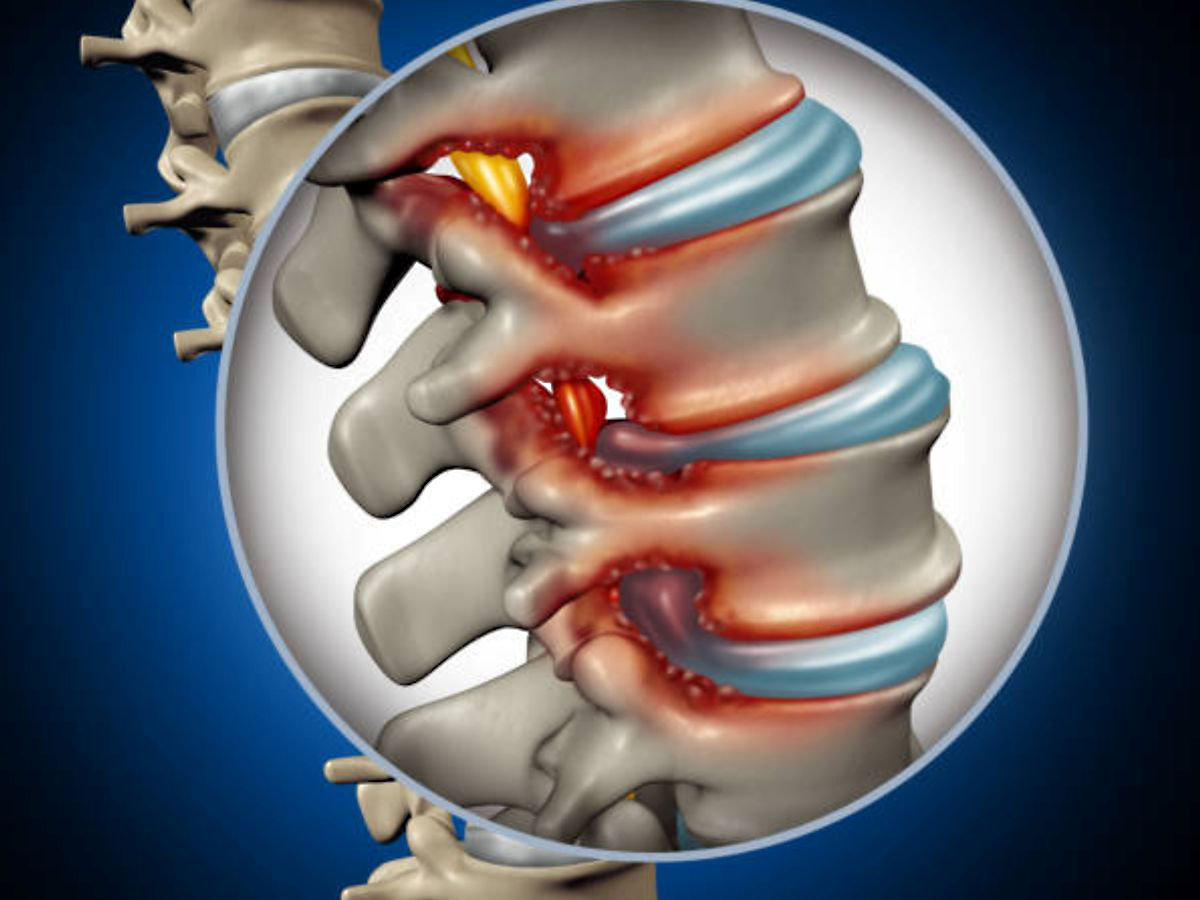

腰の神経は腰椎にある脊柱管を通っています。腰椎の椎間板が膨隆、靭帯(じんたい)の肥厚、骨の変形などにより腰椎の脊柱管が狭くなり、神経を圧迫することによって腰痛、足のしびれ・痛み、歩行障害、排尿障害などが出る病気です。生まれつき神経の通り道(脊柱管)が狭い人もいます。長い年月の間、身体を支えることで椎間板の膨隆、靭帯の肥厚、骨の変形が起こり、年齢とともに徐々に進行すると言われています。このため全ての人に起こる可能性がある病気です。